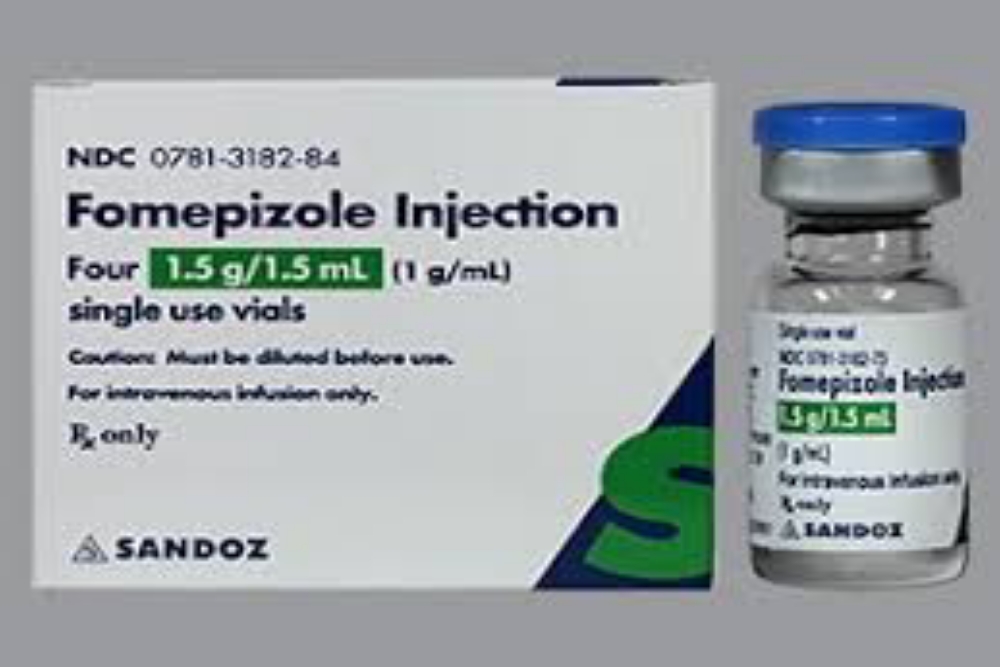

"Begitu kami tahu penyebabnya apa, toxic-nya apa, kami mencari obatnya untuk para balita yang masuk rumah sakit. Sudah ketemu obatnya, namanya Fomepizole [injeksi]," ungkap Menteri Kesehatan RI Budi Gunadi Sadikin pada konferensi pers, Jumat (21/10/2022).

Mengutip laman drugs.com, fomepizole merupakan penangkal racun jenis tertentu. Digunakan untuk mengobati keracunan akibat metanol atau zat yang terkandung dalam pelarut pada bahan kimia sera etilen glikol yang juga merupakan zat pelarut.

Meskipun demikian, fomepizole juga kerapkali digunakan bersama dengan hemodialisis guna membersihkan tubuh dari racun.